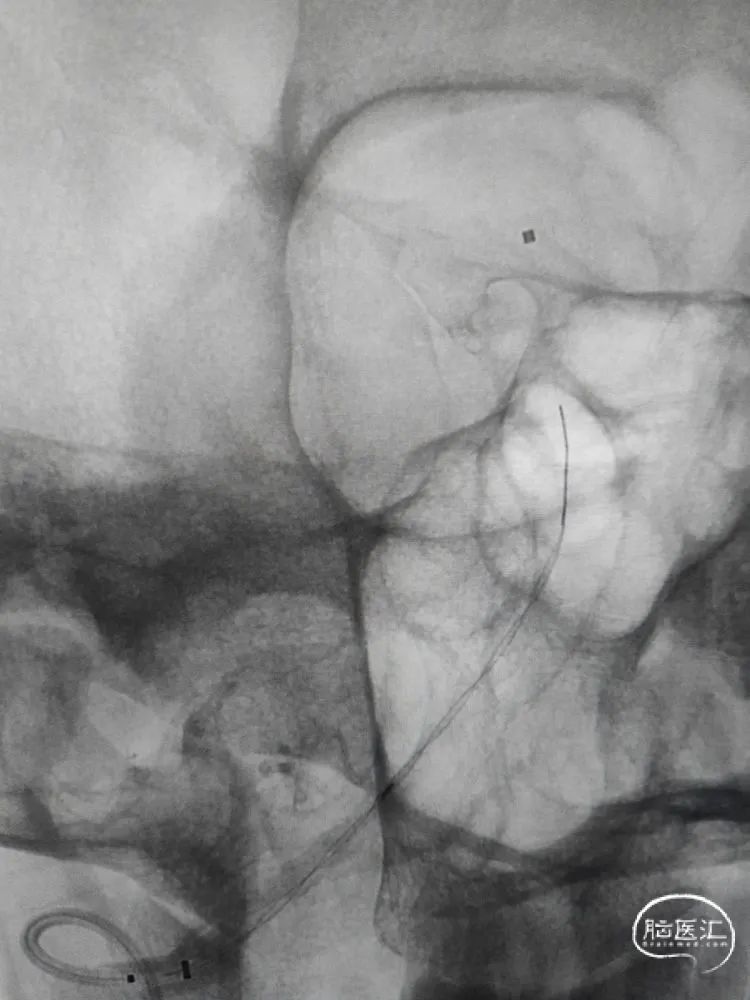

输送支架:

沿Fastrack微导管输送改进版Tubridge血流导向密网支架至基底动脉,整体通路系统稳定,U-track颅内支撑导管良好的支撑性保障了支架顺利到位,同时也保证了支架在释放中的稳定性。

支架释放:

改进版的Tubridge血流导向密网支架到位后,支架在远端预打开再回撤定位,从双椎动脉汇合处下方开始释放,缓慢推出支架进行头端锚定,改进版的Tubridge血流导向密网支架有效改善了头端打开和锚定性能,支架远端刚好落在汇合处下方,造影观察支架充分锚定后,继续缓慢释放支架至瘤颈中段,造影确认后,随后等张释放支架完毕,支架完全覆盖动脉瘤。改进版的Tubridge血流导向密网支架优化了编织丝和编织密度,支架支撑力显著提升,支架打开效果优异,全段充分张开贴壁。